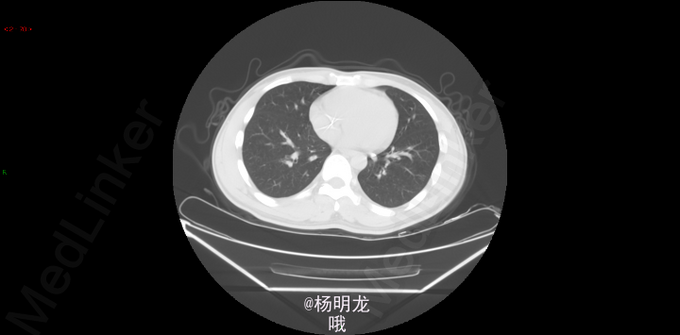

2014.9因大便带血,行肠镜检查,病理提示直肠癌。 2014-10-8胸部CT:双肺新出现多发微小结节,大者约0.2cm,高度警惕肺内转移。 遂于我院行FOLFIRI方案化疗,10周期。